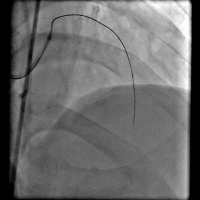

手术过程(三): 微导管支持下ASAHI Gaia 1st 导丝通过前降支真腔。

手术过程(五): 沿导丝送入Firebird 2.5×33 mm药物支架一枚至前降支中段10 atm×12 s释放,沿导丝送入Firebird 3.0×23 mm药物支架一枚至前降支近段14 atm×12s释放。